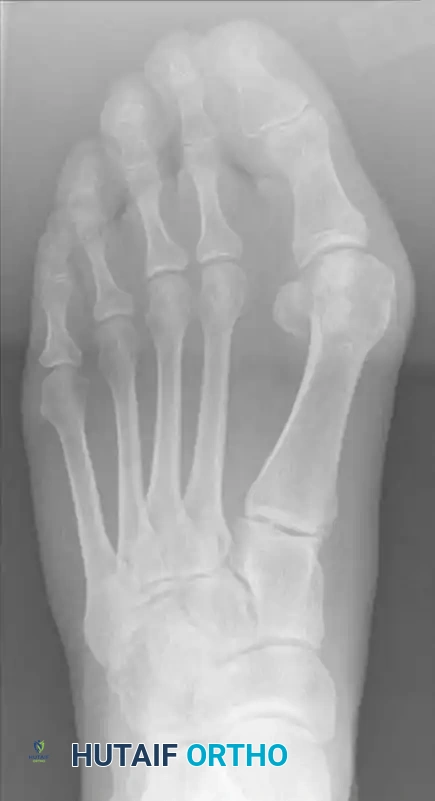

التصوير بالأشعة السينية هو حجر الزاوية في التشخيص. يتم أخذ صور أشعة للقدم أثناء تحمل الوزن للوقوف على الوضع الحقيقي للعظام. يقوم الطبيب بقياس زوايا محددة، أهمها الزاوية بين عظمة المشط الأولى والثانية، وزاوية انحراف الإبهام. تعتبر عملية سكارف مثالية للتشوهات الخفيفة إلى المتوسطة، حيث تتراوح الزاوية بين الأمشاط عادة بين إحدى عشرة وثماني عشرة درجة.

تخطيط الجراحة بناء على الأشعة

يأخذ الجراح أيضا في الاعتبار عرض عظمة المشطية الأولى. نظرا لأن هذه التقنية تعتمد على تداخل العظام، فإن العظمة الأعرض توفر مساحة أكبر للتصحيح والاستقرار. يتم استبعاد بعض الحالات من هذا الإجراء، مثل وجود هشاشة عظام شديدة، أو خشونة متقدمة في المفصل، أو عدم استقرار شديد في أربطة القدم.